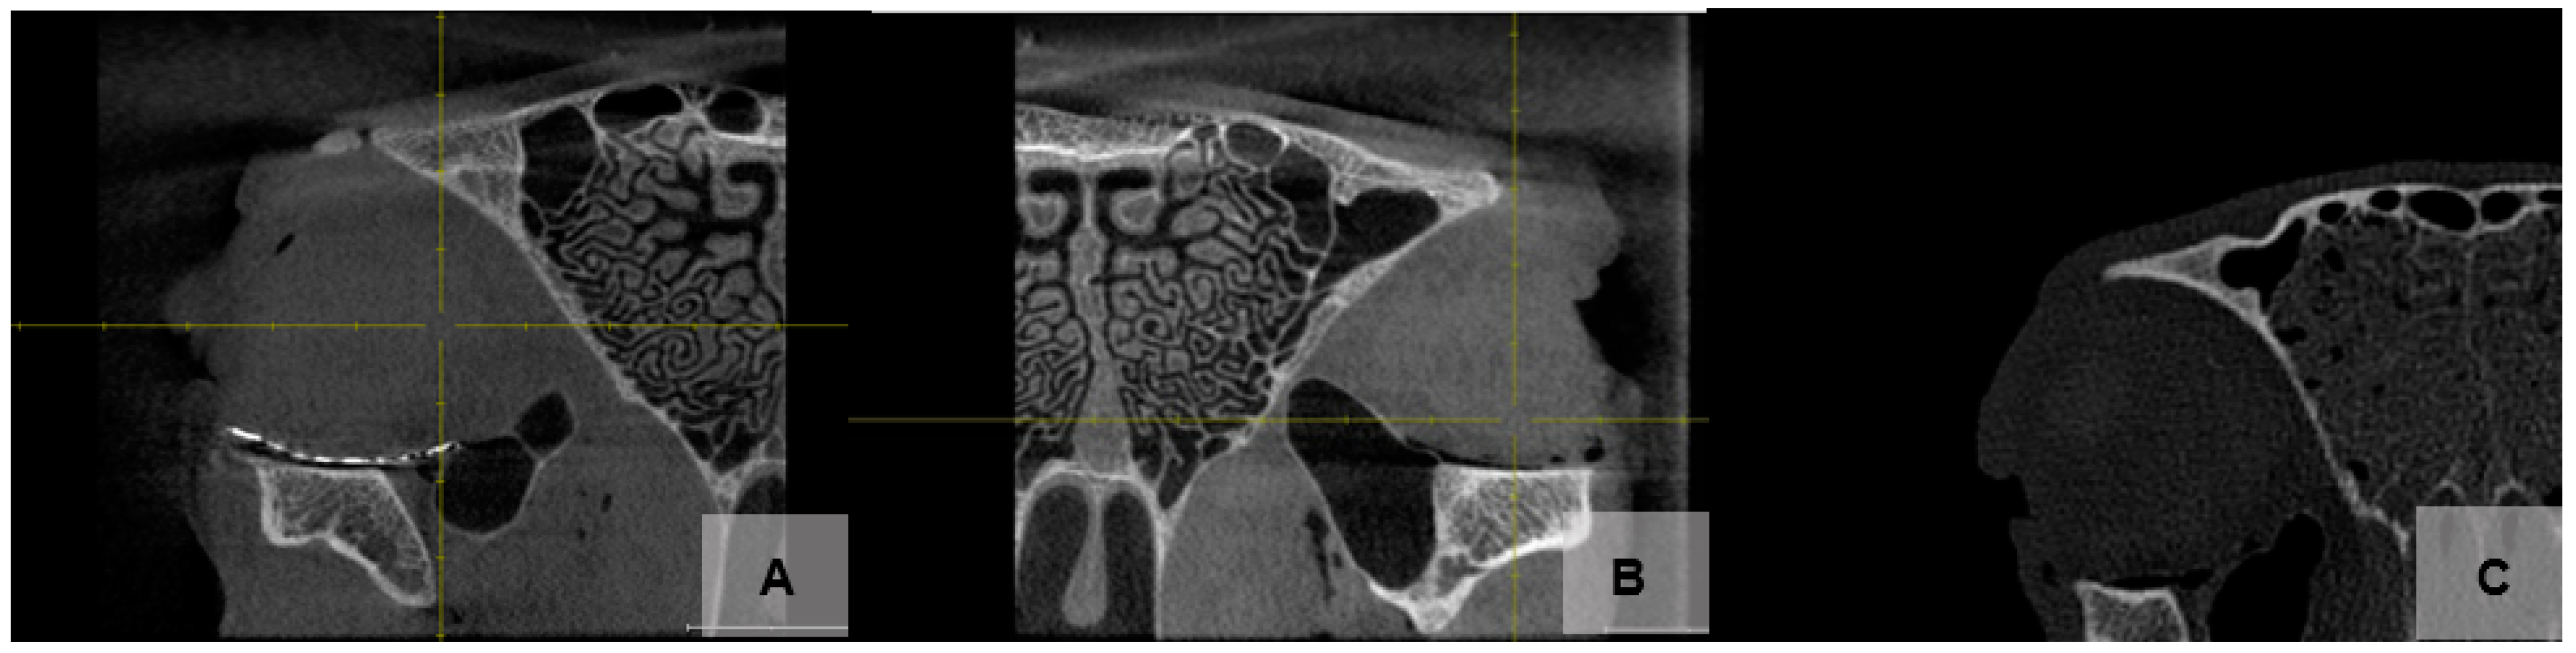

2.5. Study Outcomes

- Sufficient stability of the orbital plate against fracture and torsion during implantation.

- Good position of the implant on the orbital floor.